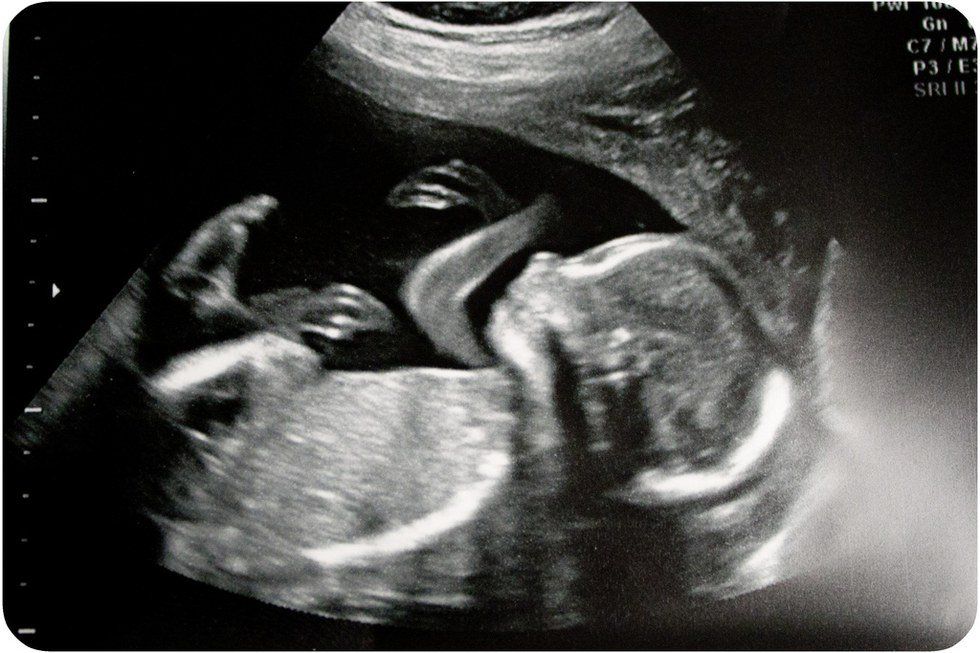

I am growing bigger and stronger every day. The most amazing thing happened today, I could wiggle my tiny, fragile fingers. It felt so good. It seems that every day also brings more and more anxiety. Do not get me wrong, I love it in here and appreciate this temporary home, but I cannot wait to see the sparkle in your eyes, your dimples that I hear people compliment constantly, and to feel your warm hugs. I feel butterflies in my stomach when I think about breathing my first breath of air outside.

I can sense that life is a little stressful for you outside the womb. I hope that I am not adding to your stress, that is my last intention. Today’s doctor appointment was kind of weird, don’t you think? Some type of procedure seemed to be the hot topic of discussion. It sounds scary, but I trust you. At least we are going through it together and they said it would be quick. I wish you would not cry so much, it breaks my heart that is now beating by itself.